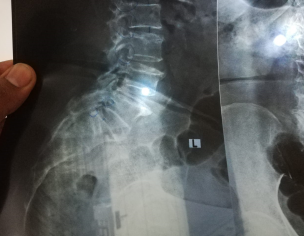

Aoa. My mother is DM-2 on insulin, Hypertensive, Stage 2 renal failiure (taking medicine regularly so all conditions in control). She developed pain lower back radiating to left leg since 1 month. pain sharp, localized and associated with movements. pain is relieved while sitting or resting (lying on bed ). She is taking Tablet. Gabapil 75mg BD and other pain killers advised by local General Practitioners but seems not helping much. X-ray and MRI shows narrowing of L4,L5 spaces and nerves compressed. Went to local pain clinic and Doctor recommended Laser procedures for decompressing nerves. Name of procedure is "Transforming Nerve root Procedure and Intradiscal Laser (rf) for 50,000 rupees. Can any Neurosurgeon Please comment on this treatment. We also consulted a Neurosurgeon in RYK. He says immediate decompressive surgery at multilevel is required. Should we go for surgery or wait and see while doing physiotherapy . MRI and other images are attached. Thanks in advance

2. MRI images r showing multilevel dehydrated discs nd stenoses most marked at L4-5